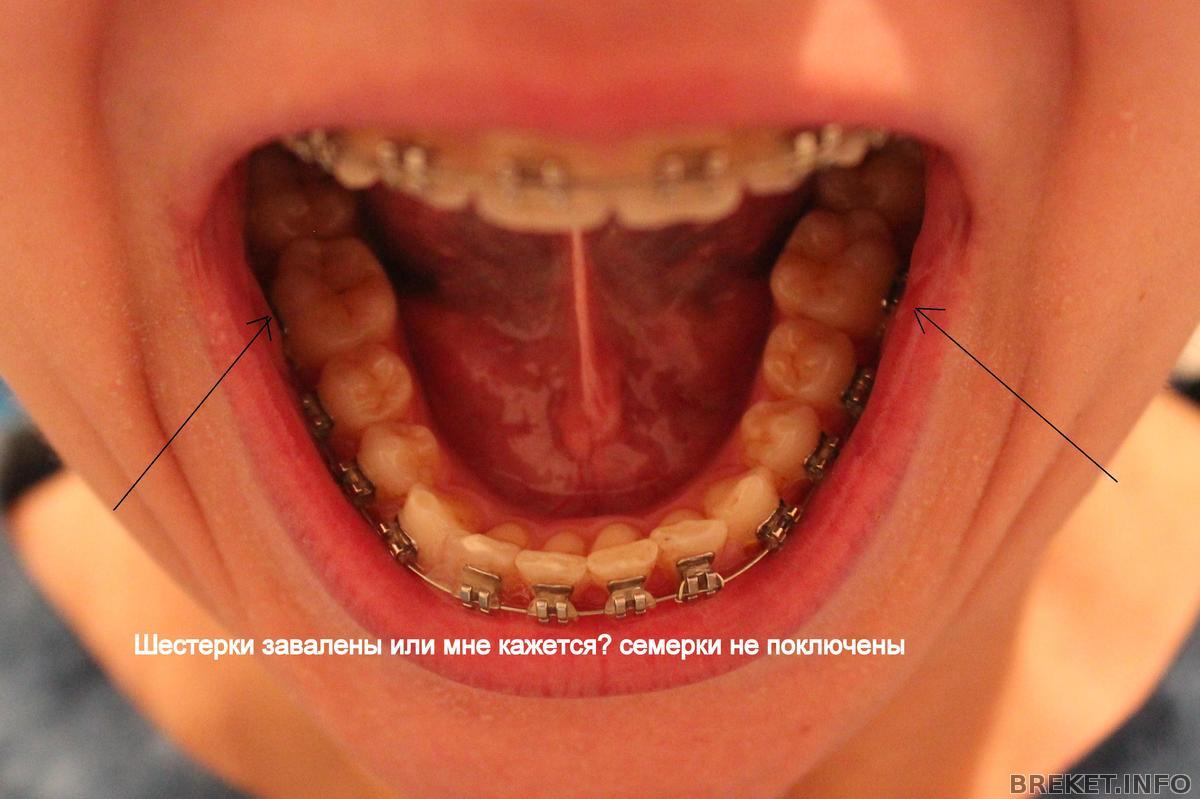

А дело вот в чем. Брекеты мне приклеили начиная от 6ок, т.е. 7 не подключены к системе. Так вот зубы у меня выравниваются, а 7 с ними даже в одном ряду не стоят, как я говорю "пляшут". Мне это очень не нравиться и я очередной раз поинтересовалась у орта, почему 7ки не в ряду с остальными зубами и как это исправлять. Она сказала, что чтобы исправлять это надо клеить брекеты начиная от 7. И мол сейчас это делать накладно, да и не нужно вовсе, потому цитирую "когда мы снимем брекеты, 7ки все равно встанут так как им удобно". Тогда вопрос - а нафига я ношу брекеты, если все потом встанет, как им удобно?!

В общем я настаиваю на том, чтобы мне подключили семерки, она мне объясняет, что в это смысла нет, что они натирают, что на них внимание вообще не обращают, что при улыбке у меня их не видно, что потом они все равно встанут на свое место и т.д.

Еще у меня завалены 6ки на нижней челюсти, на что она тоже не обращает внимание. Короче, вопрос, у кого как с этим делом обстоят дела???